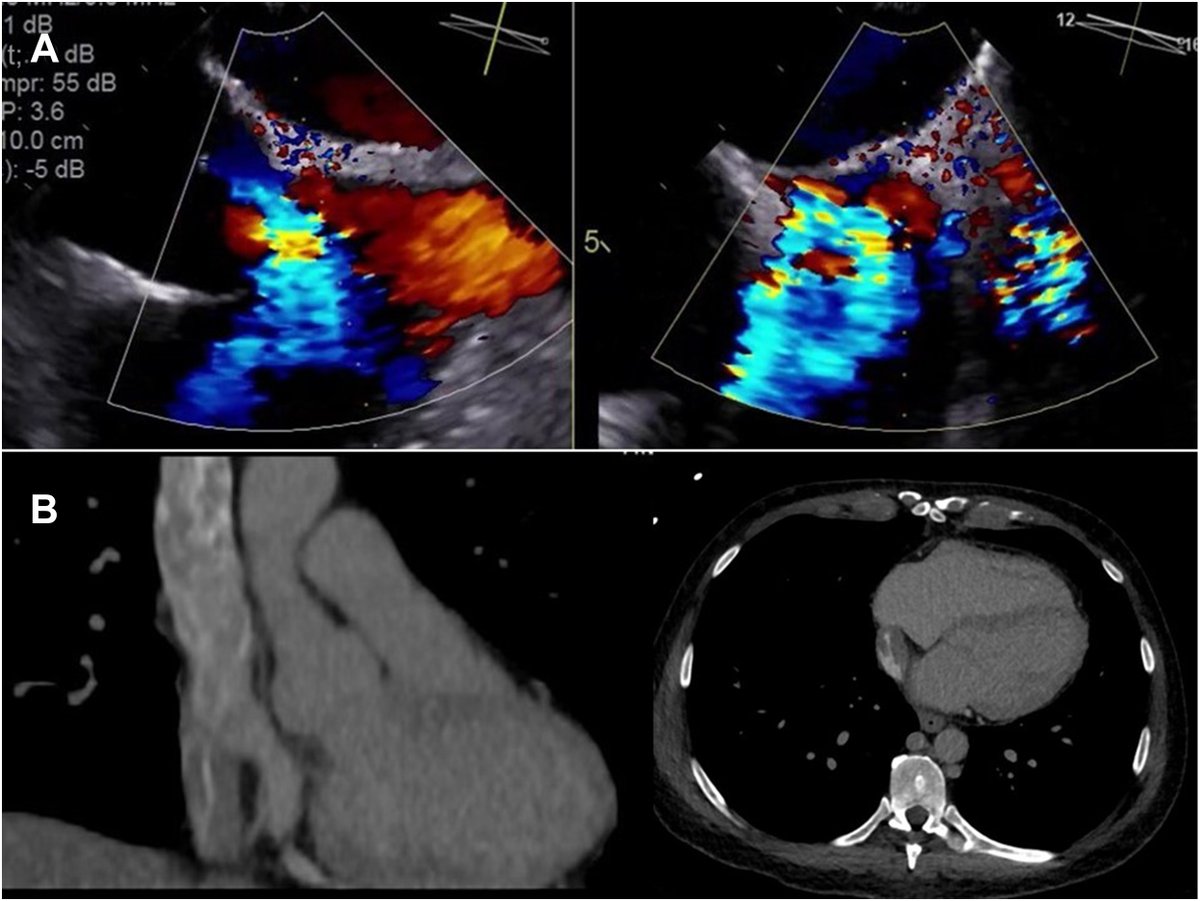

#VisualAbstract from Witten et al on Invasive Aortic Valve Endocarditis: Clinical and Tissue Findings From a Prospective Investigation: https://t.co/GpXFj3BEog #AnnalsImages #TSSMN @nksmd @MdGosta